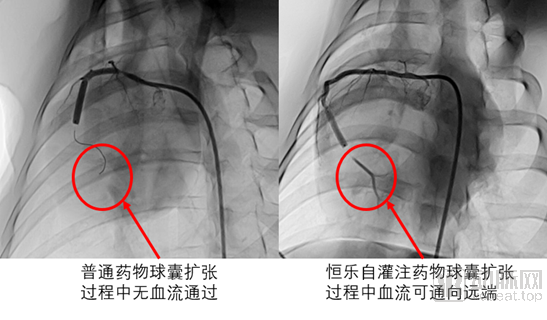

恒升醫(yī)療完成近3億元A輪融資,全面助力心血管精準(zhǔn)診療一站式服務(wù)

繼2020年國家組織冠脈支架集中帶量采購恒升醫(yī)療集團旗下子公司萬瑞飛鴻的NOYA雷帕霉素藥物洗脫支架以最高價中標(biāo)后,領(lǐng)先的冠脈醫(yī)療器械研發(fā)制造廠商恒升醫(yī)療集團近日又有新動